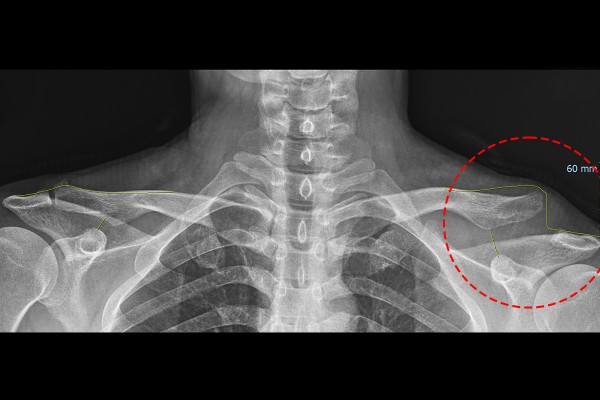

환자분의 어깨 상태를 파악하기 위해서 X-RAY 검사를 시행하였고, 검사 결과, 우측 어깨에는 이상이 확인되지 않지만 좌측 어깨관절은 견봉과 쇄골, 오구돌기와 쇄골이 탈구되어, 높낮이와 거리가 벌어져 있음이 확인됩니다.